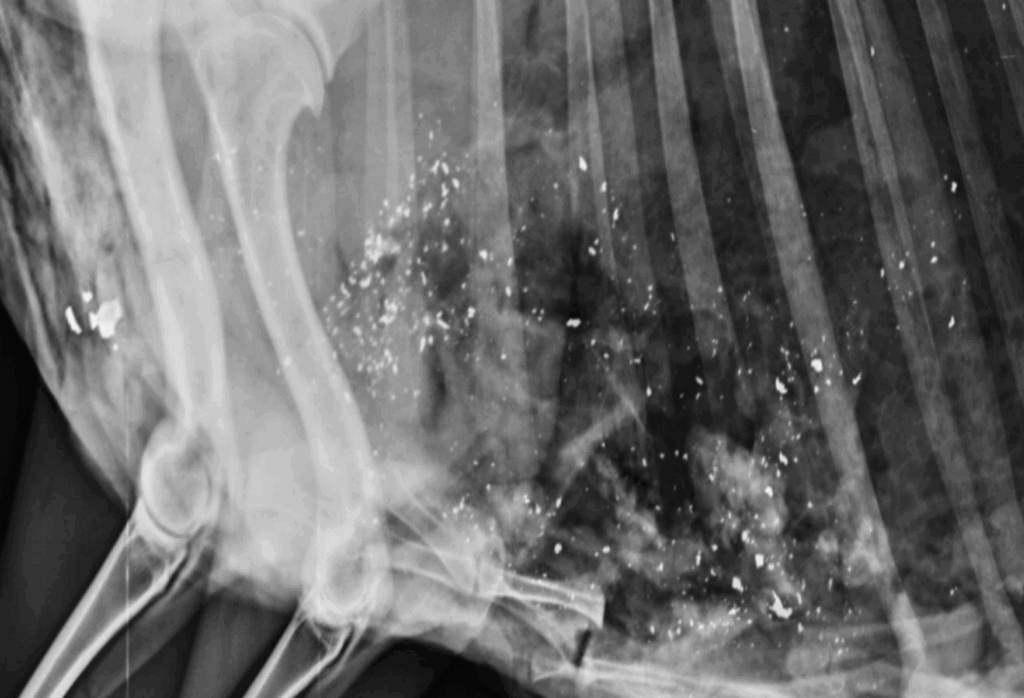

Lead bullets shatter on impact, leaving thousands of tiny fragments in the meat. These particles can spread up to 340 mm from the wound and are too small to see or wash away. Studies show that 100% of game meat samples from South African wildlife tested above European safety limits for lead.

Each white spot on these x-rays is a lead fragment deposited in a Springbok shot with a .243 calibre lead core bullet (Acknowledgement: CHASA and NATSHOOT).